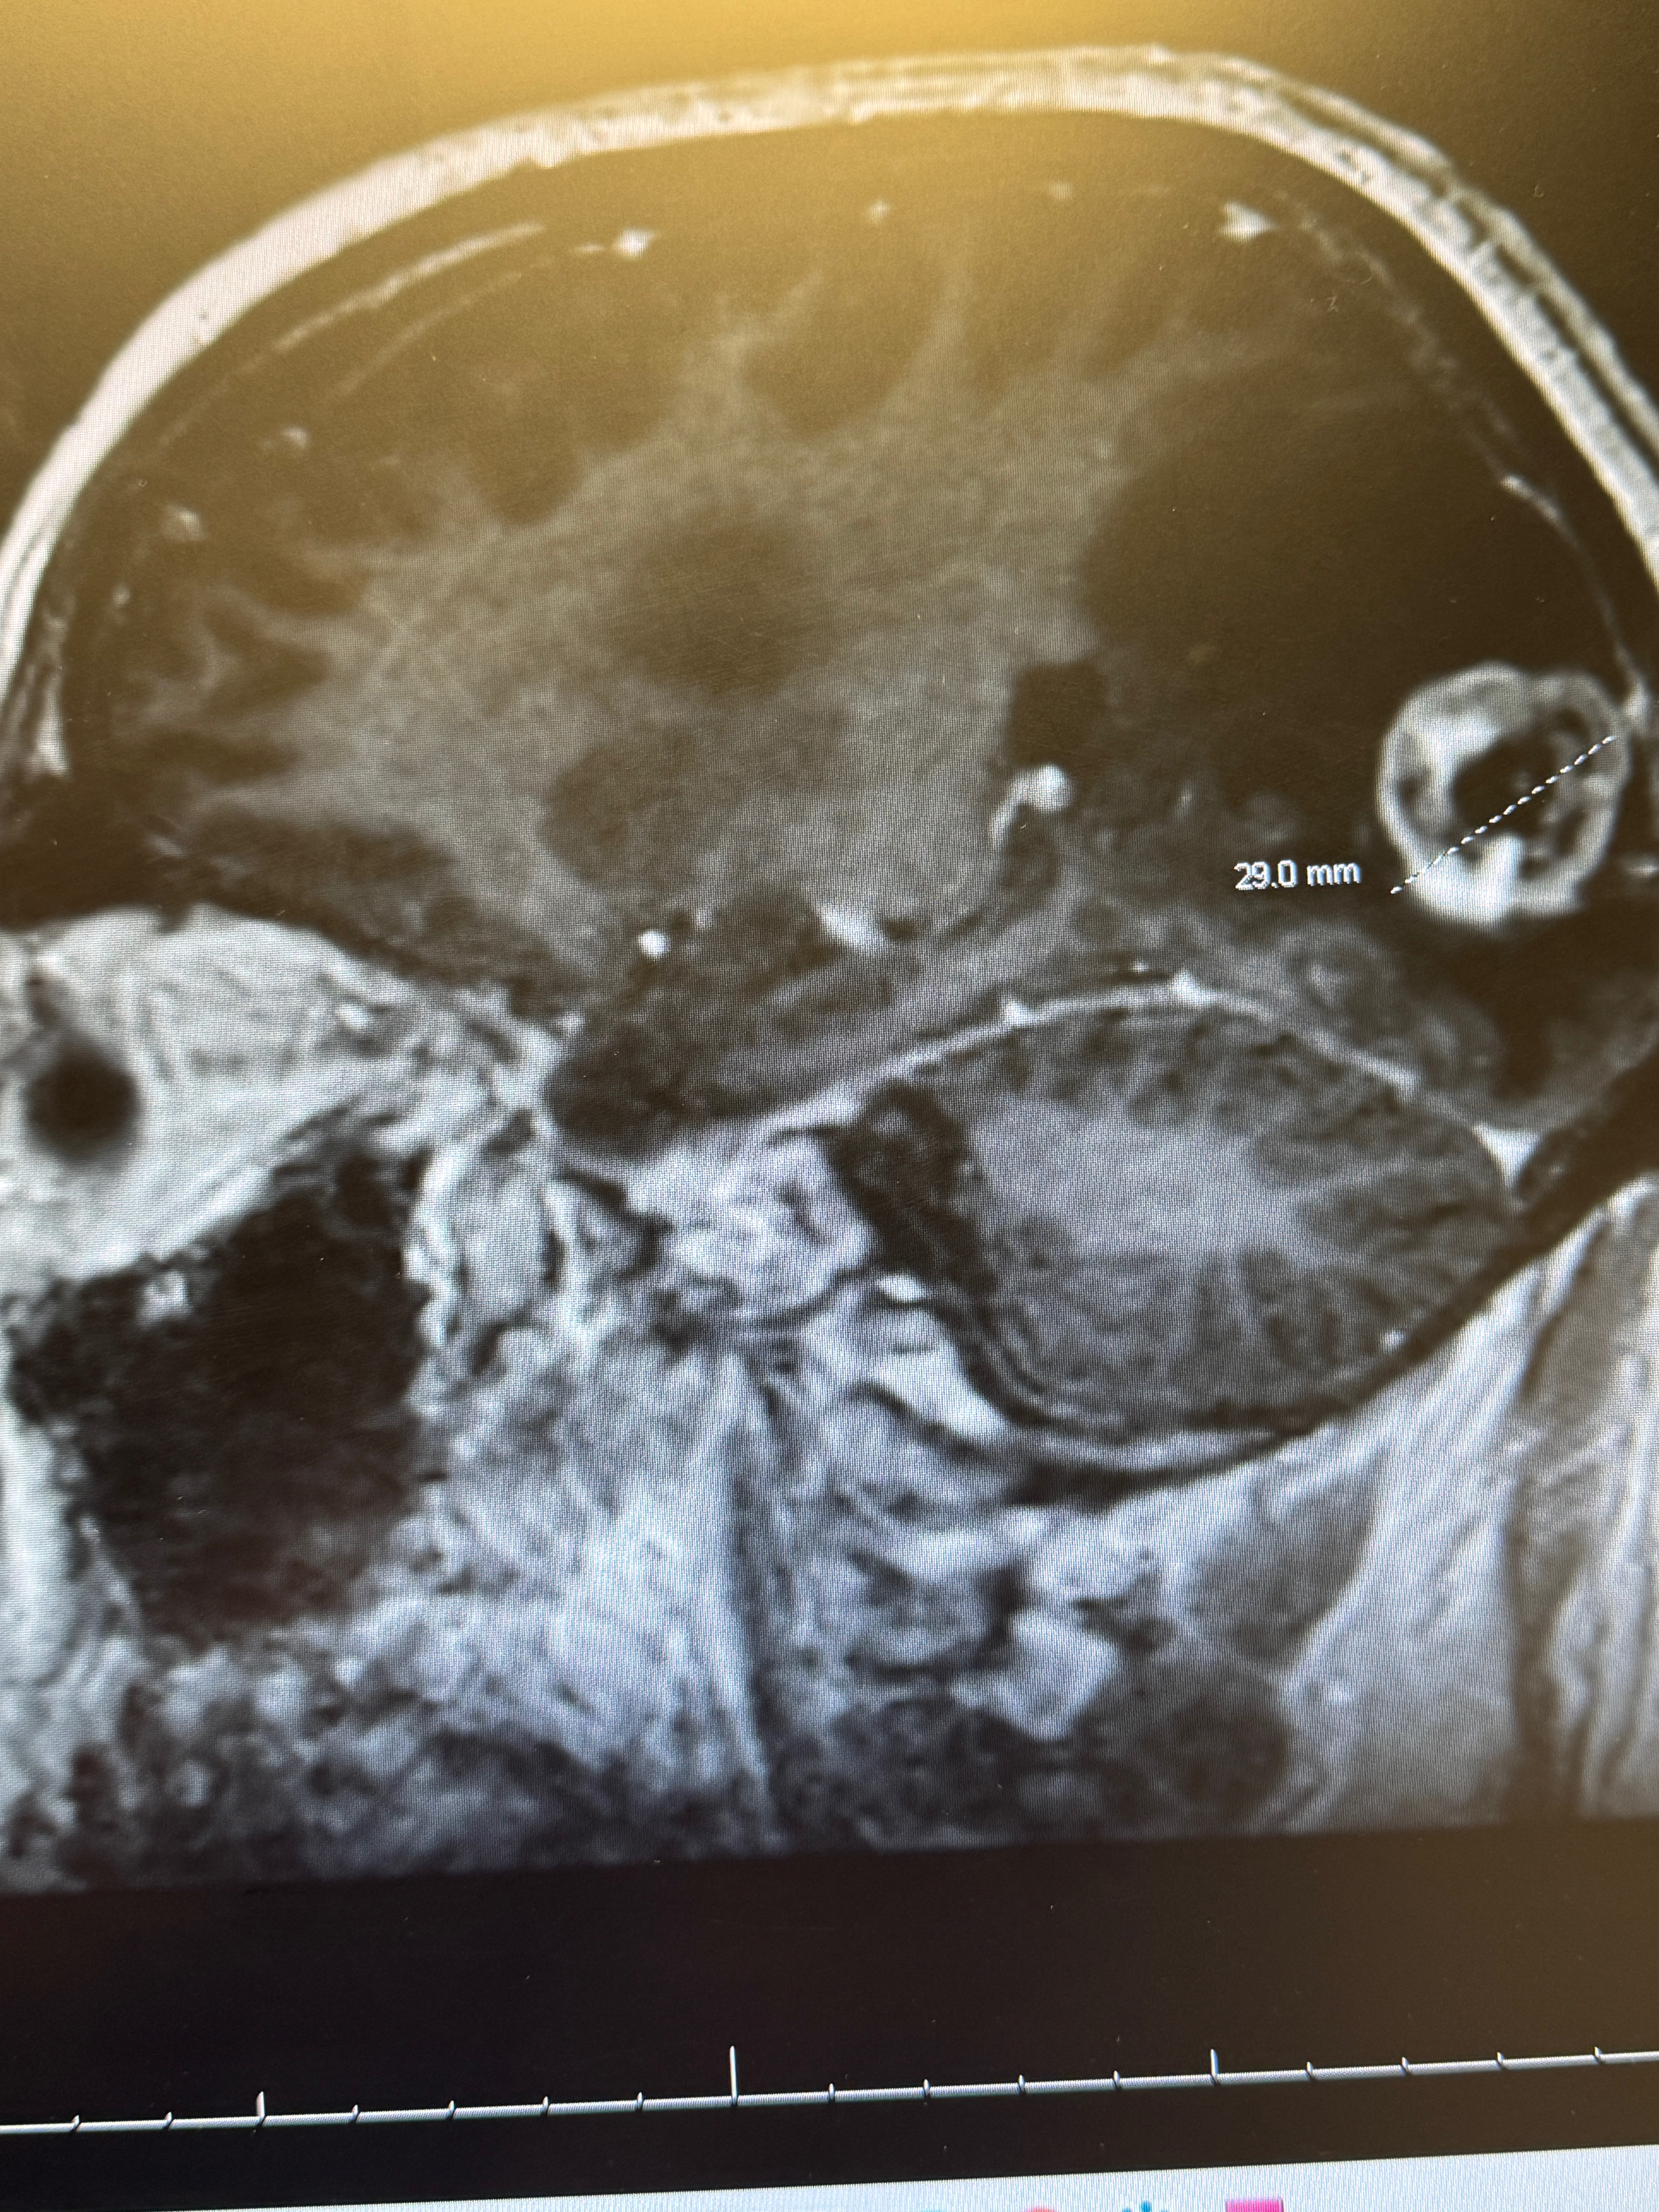

As many of you already know on August 18th, I was diagnosed with a highly aggressive and advanced form of brain cancer. After complaints of confusion and aphasia an MRI revealed multiple tumors, some quite large throughout my brain, and there was massive swelling. My blood sugars were way too high. My doctor sent me to the emergency room, where they told me the terrible new and admitted me immediately.

While I was in the hospital, further testing revealed that my cancer most likely began in my kidneys, a renal carcinoma. From there it moved into my lymph nodes and it is present in my femur bones and in both lungs, the neck and throughout the head. Additionally, a skin cancer has developed on my right-hand index finger, under the fingernail which will result in a partial amputation of the finger. To be clear, my condition is terminal.

On September 15th my treatments began. They sent targeted radiation directly to the brain tumors, and I received my first chemotherapy infusion. In the days that followed my mind and body deteriorated into disability levels. I had extreme confusion and fatigue, painful mouth sores and swelling of my feet and legs. My recovery time has been more than 10 days to get to this point and I am still not 100% This was round one of ten. Nine more chemo infusions, the next one will be this Friday October 10th. I expect next week, and all the weeks following these treatments will be difficult.